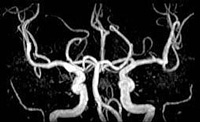

MRI検査は、磁石と電波を用いて身体の任意断層面を撮像する検査です。「脳ドック」 をはじめ人体の血管を3次元の立体画像に作成し、診断に用いられています。CTとは異なりX線を使用しません。検査時間は約20~30分です。検査時にはコンタクトレンズ、ヘアピン、ネックレス、時計、カード類などは外していただきます(準備室に鍵付きロッカー有)。なお、心臓ペースメーカーをしている方は検査できません。手術で体内に金属がある方も検査できない場合があります。